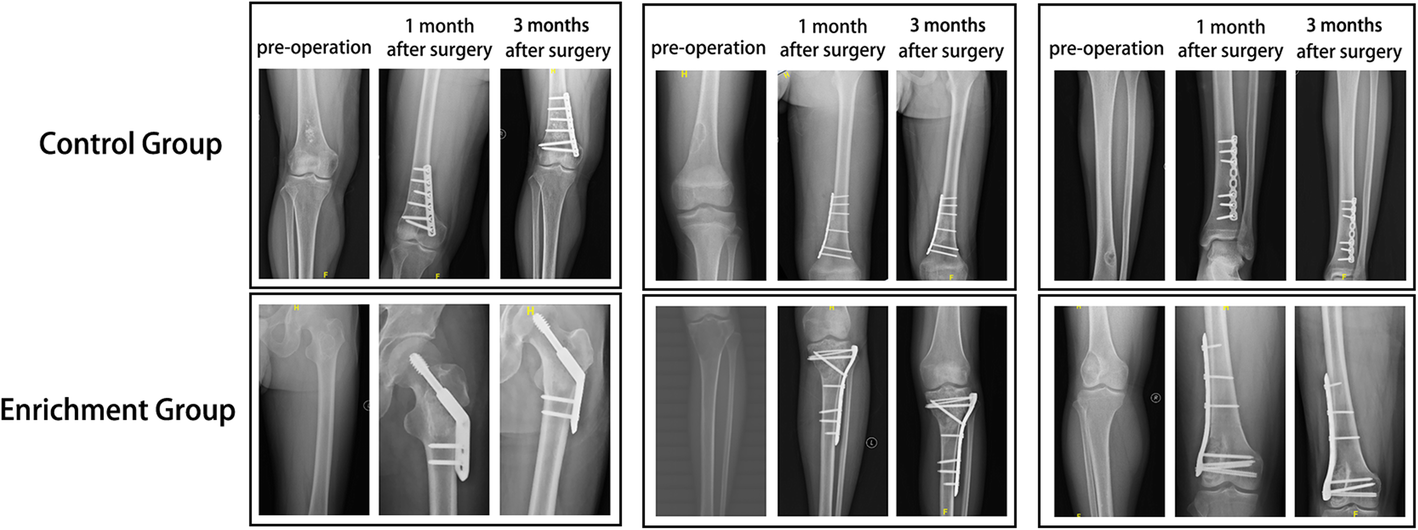

Fig. 3

X-ray findings for the MSC/TCP bioactive scaffolds in repairing bone defects after benign bone tumor resection. The upper row showed three patients in the experimental group, while three patients in the control group are placed in the lower row